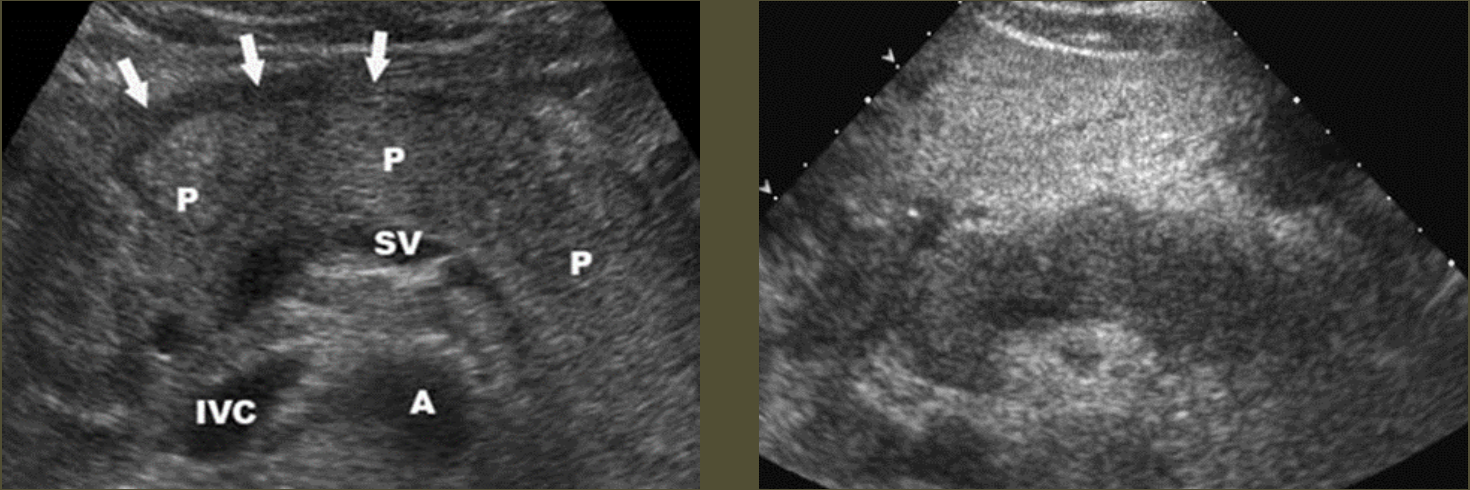

Chronic Pancreatitis → recurrent attacks of acute pancreatitis, progressive destruction of pancreatic tissue

2D US: mixed pattern of echogenicity (hyperechoic from fibrosis to hypoechoic from inflammation), calcifications, normal to atrophic size, nodular surface, dilated/calcified pancreatic duct (> 3 mm), solid mass, thrombosis of splenic and portal vein